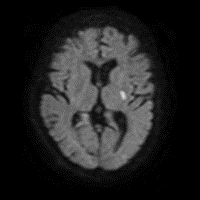

5/ Because the lesion is calcified and suspected to represent ruptured plaque, they are loaded with ASA/Plavix and admitted for close monitoring. MRI shows small infarct: